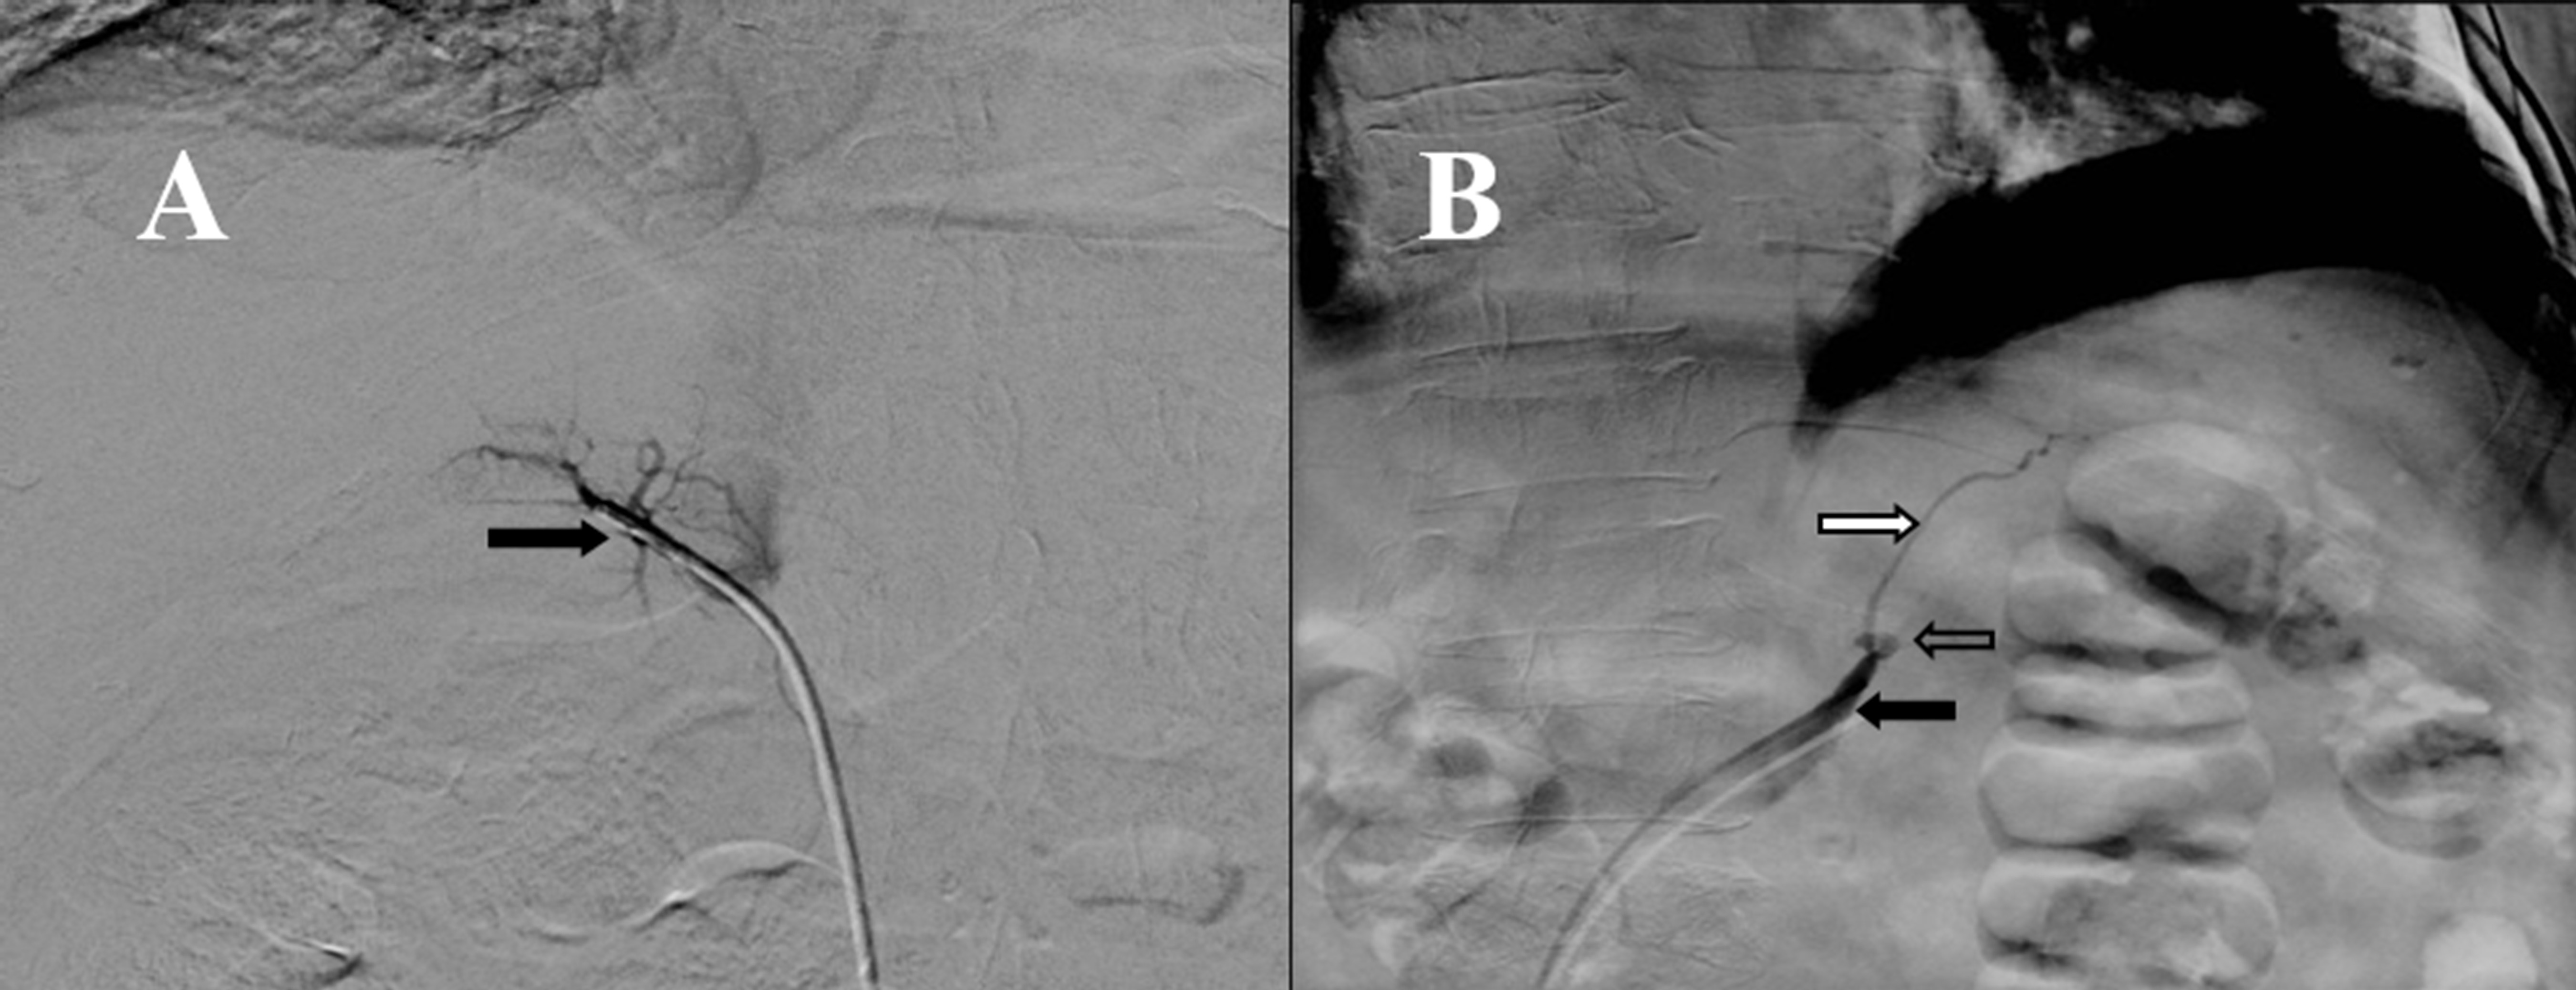

Figure 2.

Adrenal vein sampling. A: Right adrenal venography using 4Fr multipurpose catheter from femoral approach, where adrenal central vein can be seen right (black arrow) with glandular branches that converge to it. B: Left adrenal venography using multi-purpose catheter 4Fr from femoral approach, where common adrenal trunk (black arrow) can be seen with the catheter in the interior, where the lower left phrenic vein (white arrow) and left adrenal vein (arrow without filler) converge.

A previously described protocol was used 7 with some changes. The authors of the original protocol propose the measurement of epinephrine as a method to determine the proper location of the catheters when performing the sampling. Because we do not have readily available the measurement of plasma catecholamines the test was performed using radiographic documentation of the tip of the catheter and aldosterone levels were used to make the corrections in the dilution between both sides 2. Samples of both adrenal veins and inferior cava vein were taken (the procedure is shown in Figure 2 and the results are shown in Table 2). Based on the model of interpretation of adrenal venous sampling proposed by Young 3 the test suggest that the patient has an adrenal hyperplasia with predominance in the production of cortisol from the right side, the results were discussed with the patient and the surgical team and it was then decided to perform a bilateral adrenalectomy. The result of the histological study of the glands was consistent with a bilateral adrenal macronodular hyperplasia.